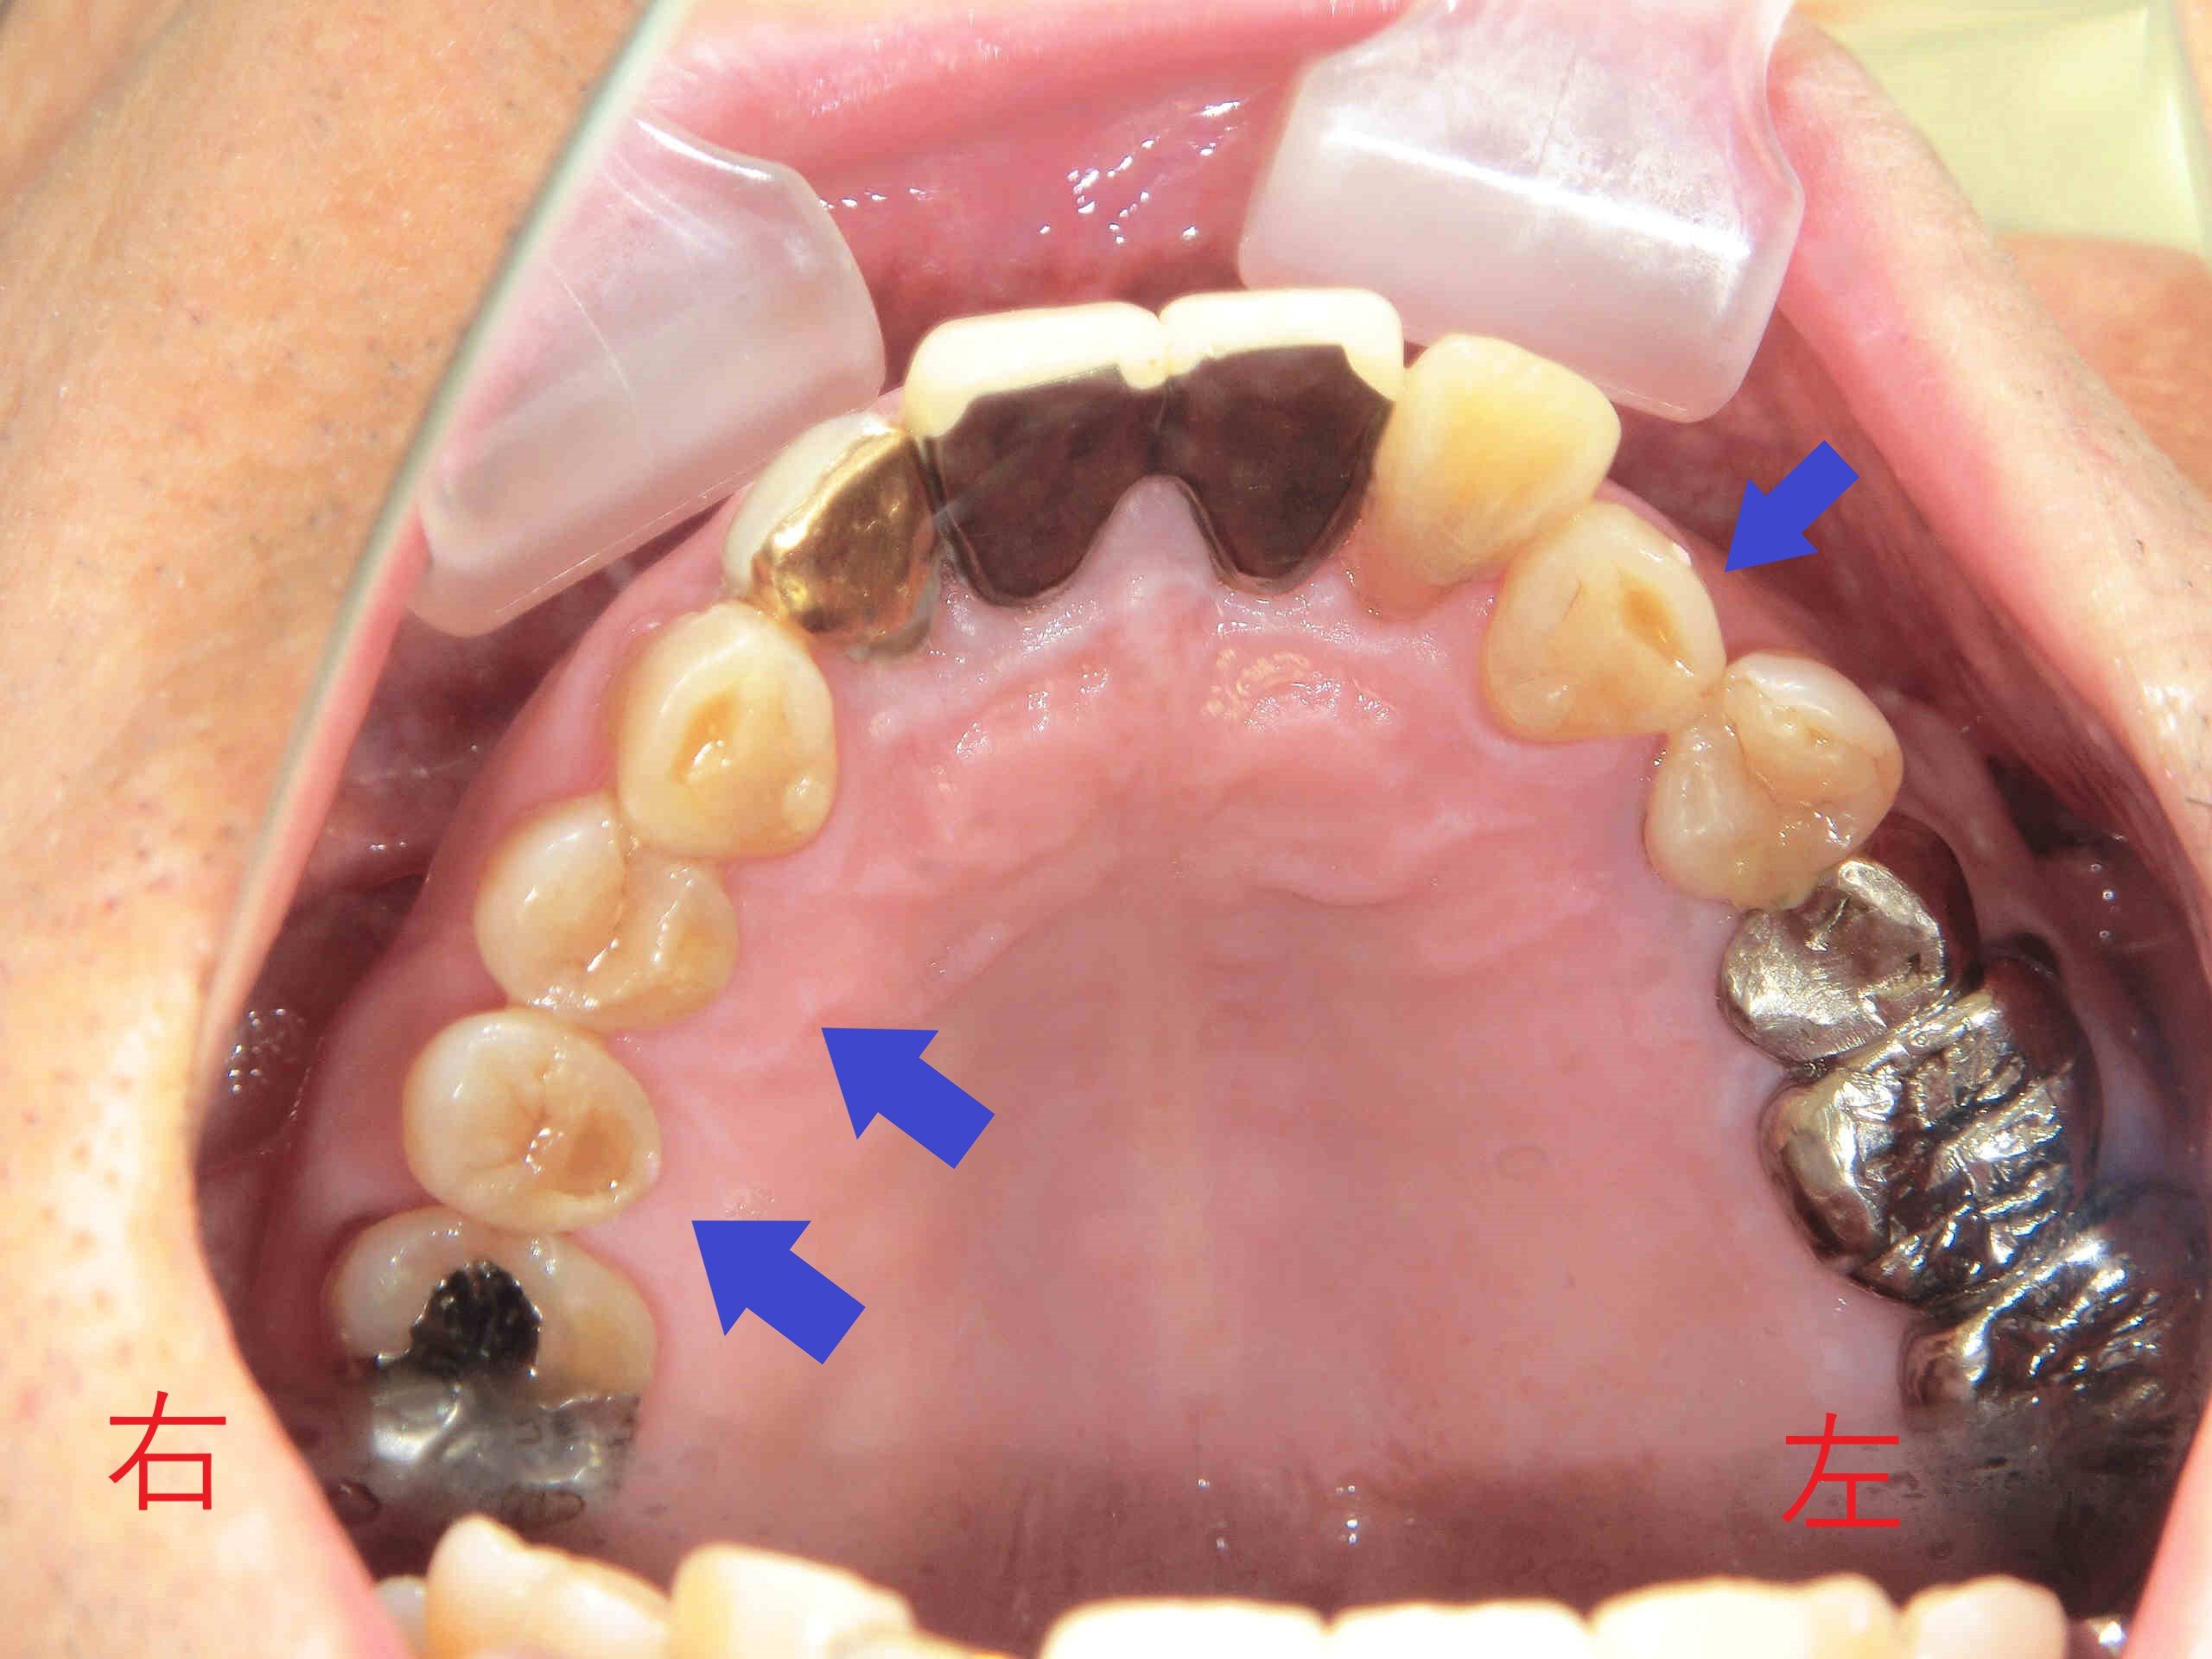

上記はインプラント治療を含めたすべての治療が終了した写真です。ここでも、青色矢印の下顎前歯の部分にご注目ください。冒頭の写真と比較すると、奥歯で噛んだ際に上顎前歯によって隠れていた下顎前歯の部分が少なくなっていることがお分かりいただけると思います。

歯ぎしりや食いしばりによってすり減った歯を被せ(冠)にすることで、咬合高径を引き上げ、“出っ歯”のように見えていた上顎前歯を内側へ移動させることができました。

「噛み合わせを高くすると、口を閉じにくくなるのでは?」とご懸念の方もいらっしゃるかもしれません。そこで、被せる前に仮歯を装着し、噛み合わせを綿密にチェックしております。実際、この患者様は通常通りに口を閉じることができ、口元の“出っ歯感”も解消され、自然な口元になりました。

左上は治療前(初診時)に近い状態の上顎を下から見上げた写真、右上は同じ状態の下顎を上から見た写真です。いずれも青色矢印の歯をご覧ください。歯ぎしりや食いしばりのために歯がすり減り、歯の表面が陥没している様子が観察されます。

左上の写真は治療終了後の上顎を下から見たもので、右上は治療終了後の下顎を上から見たものです。今回の治療で咬合高径を高くした目的は、患者様の主訴である“上顎前歯の出っ歯”を解消するためだけではありません。低い咬合高径のままでは、インプラントに被せ(冠)を装着すること自体が難しかったからです。

なお、下顎の写真で黄色矢印の歯がインプラントの被せ(冠)です。埋入したインプラントは2本ですが、長期にわたって良好な口腔環境を維持するために非常に重要な2本となります。